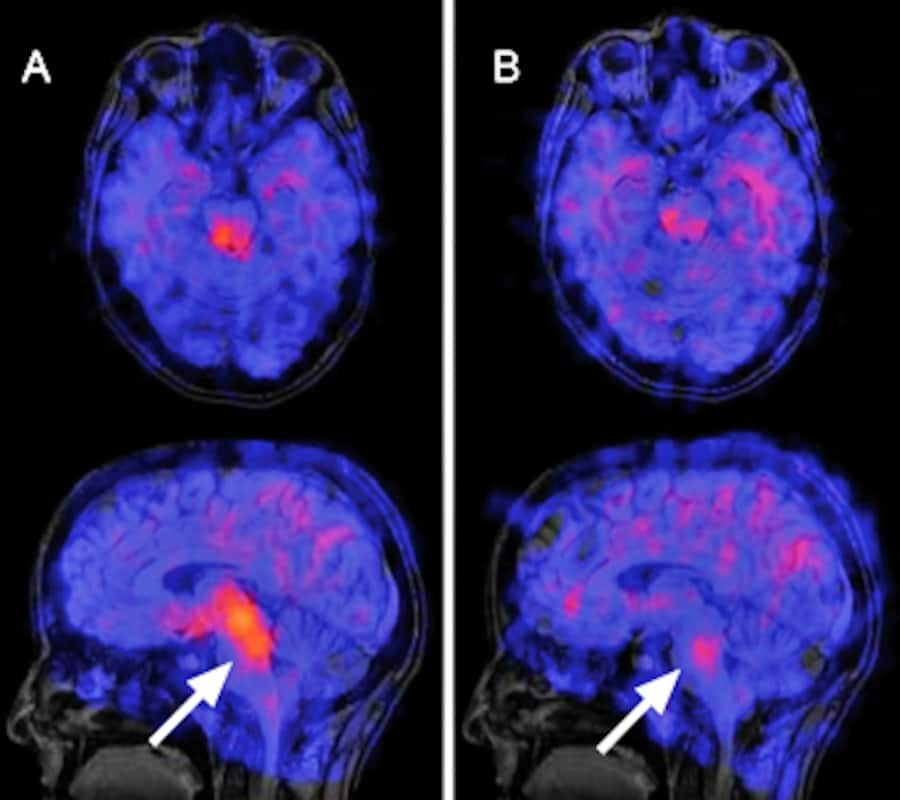

Indirekte Darstellung der Serotoninaufnahme im Gehirn vor und nach sechswöchiger Behandlung mit dem SSRI Paroxetin (Handelsname Deroxat): Die Bilder zeigen die pharmakologische Wirkungsweise des Medikaments, beweisen aber nicht dessen Wirksamkeit.